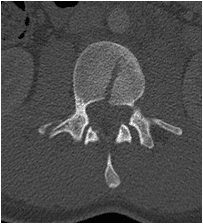

Patient was operated and the spinal canal cleaned up of all bony fragments. The spine was fixed from the side and the back to take care of instability.